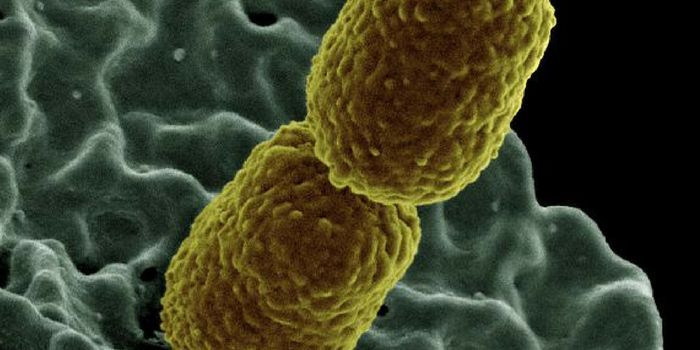

MAR 16, 2015MicrobiologyTargeting deadly, drug-resistant bacteria poses a serious challenge to researchers looking for antibiotics that can kill ...